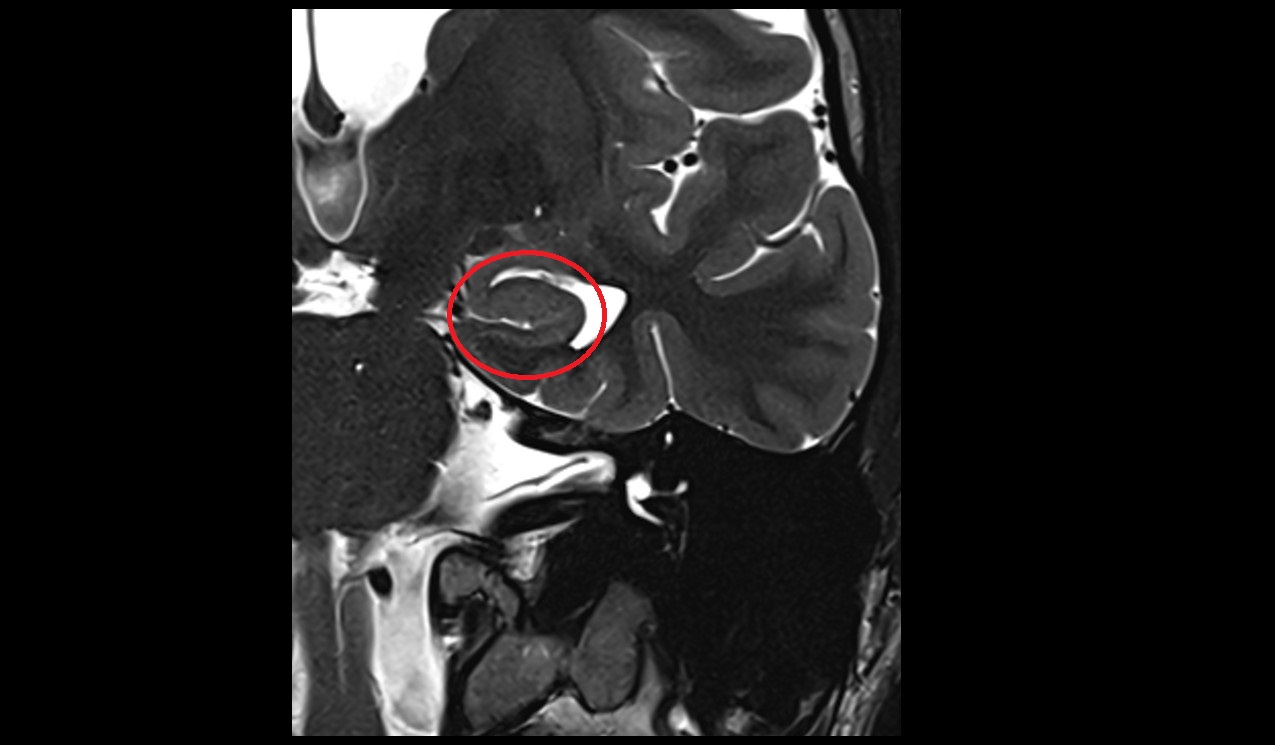

- Hippocampal head

- Head of hippocampus